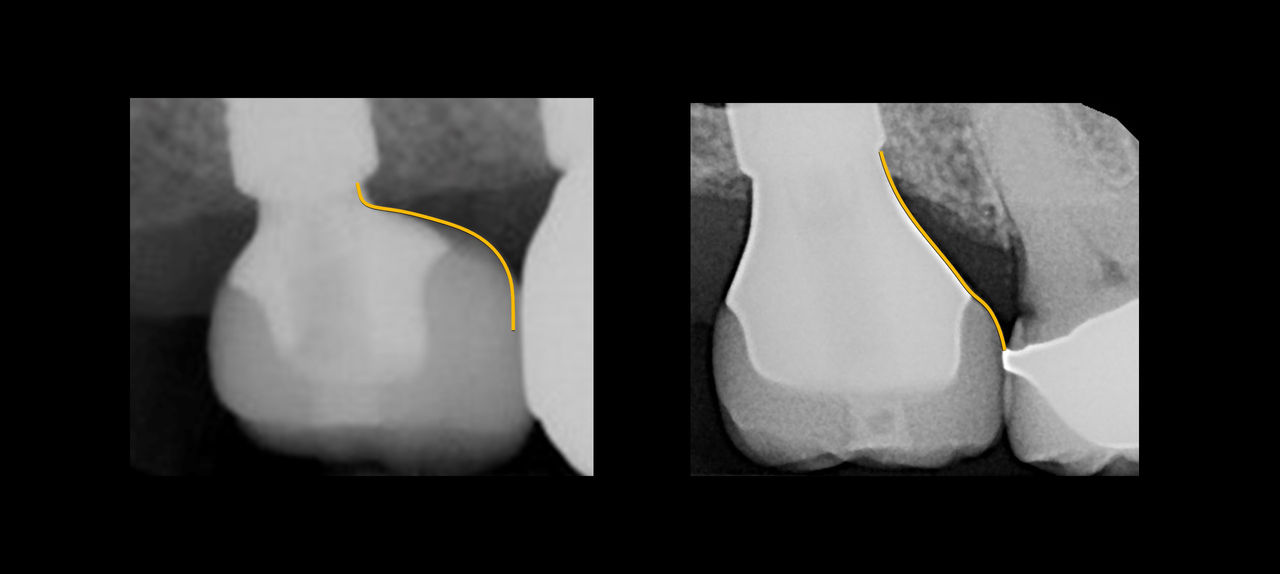

Ce cours de niveau maîtrise aborde à la fois la prévention et la gestion des complications chirurgicales et restauratrices. Dans le domaine chirurgical, la présentation se concentre sur l’échec précoce de l’implant et la maladie péri-implantaire ultérieure. Les concepts prothétiques comprendront la conception de prothèses préventives, le retrait des vis/piliers et un séquençage qui reconnaît l’importance de l’expérience du patient.